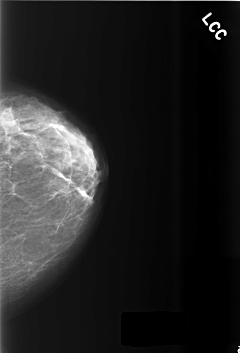

C_0510_1.LEFT_CC

LEFT_CC LINES 5640 PIXELS_PER_LINE 3832 BITS_PER_PIXEL 12 RESOLUTION 50 NON_OVERLAY